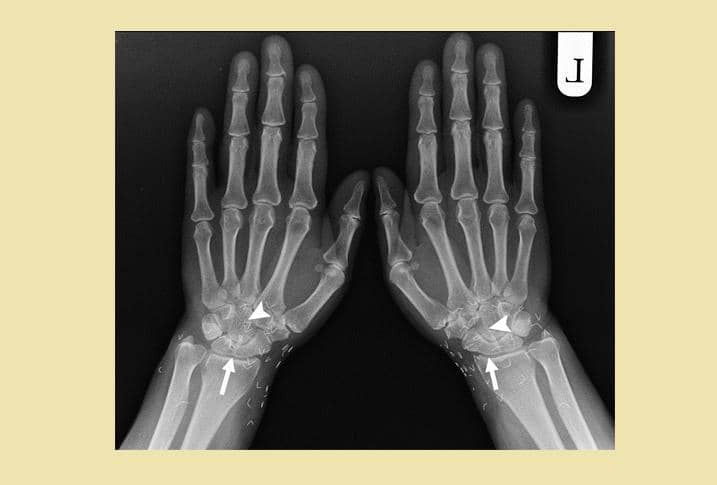

1. Ratusan susuk terlihat jelas lewat hasil foto sinar-X

Dalam unggahannya itu, Tasqia menuliskan bahwa ia sedang menangani seorang pasien berusia 55 tahun yang ingin melakukan X-ray atau sinar-X. Tak disangka, hasil foto sinar-X pasien tersebut memperlihatkan ratusan atau bahkan ribuan benda asing berbentuk seperti jarum yang bersarang pada tubuh pasiennya itu. Tasqia pun menyebut benda tersebut sebagai susuk. Sangking banyaknya, Tasqia pun tak tahu pasti berapa jumlah susuk yang ada pada bagian tubuh pasiennya itu.

Menurut Tasqia, dalam bahasa Inggris, ia menyebut susuk sebagai charm needle. Hal ini lantaran bentuknya yang seperti jarum. Susuk juga menurut Tasqia bisa berubah posisi ketika dilakukan foto sinar-X lagi.

Ketika ditanya biasanya susuk banyak ditemukan di area tubuh yang mana, Tasqia menjawab bahwa susuk bisa dimasukkan di mana saja. Namun, biasanya banyak ditemukan di sekitar kepala dan sisanya ada sekitar area kaki hingga payudara.

"LMAOOOO yess bisa dimana ajaaa cuma emang umumnya di daerah kepala, sisanya bisa di kaki tangan, perut, dada, payudara, dll," tulisnya.